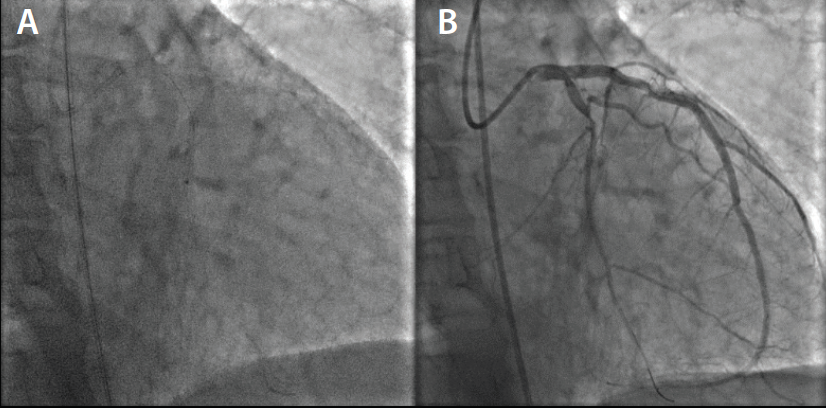

Left groin access was achieved under ultrasound guidance, and a 6-F vascular sheath was placed. Selective coronary angiography was performed in multiple views, revealing total in-stent restenosis in the mid–left circumflex artery (Figure 1). After imaging review, we decided to intervene on the lesion. Bivalirudin was started and 180 mg of ticagrelor was administered to the patient. A 3.5-F XB guide catheter was used to engage the LMCA. We were able to cross the chronic total occlusion initially using a Runthrough® guidewire (Terumo Interventional Systems). The wire was exchanged for an HT Pilot® 200 wire (Abbott Vascular) and a 0.014-inch support catheter (Figure 2). Sequential balloon angioplasty was performed from proximal to distal parts using a 1.5- X 6-mm Sprinter® OTW balloon (Medtronic), and then a 2- X 12-mm Mini Trek™ balloon (Abbott Vascular) was utilized (Figure 3). Laser coronary atherectomy was then successfully performed (Figure 4A). Postatherectomy coronary angiography revealed improved coronary blood flow (Figure 4B). Sequential balloon angioplasty was performed using a 2.5- X 20-mm Mini Trek™ balloon.

We then decided to place coronary stents. However, we had difficulty advancing the available stent even though the wire was changed to a stiffer wire and multiple techniques were attempted to no avail. We then tried a 2.5- X 24-mm EluNIR™ stent, and were able to successfully deploy the stent at the target lesion easily without any difficulty (Figure 5). We went on to deploy two more 3- X 24-mm EluNIR™ stents proximally, and finally, angioplasty with a 3.25- X 12-mm noncompliant Trek™ balloon was performed (Figures 6 and Figure 7A). Postprocedural coronary angiography demonstrated restoration of blood flow across the left circumflex artery with an excellent result (Figure 7B). At the end of the procedure, the patient left the cardiac catheterization lab stable and with no complications. The patient is discharged the next day.